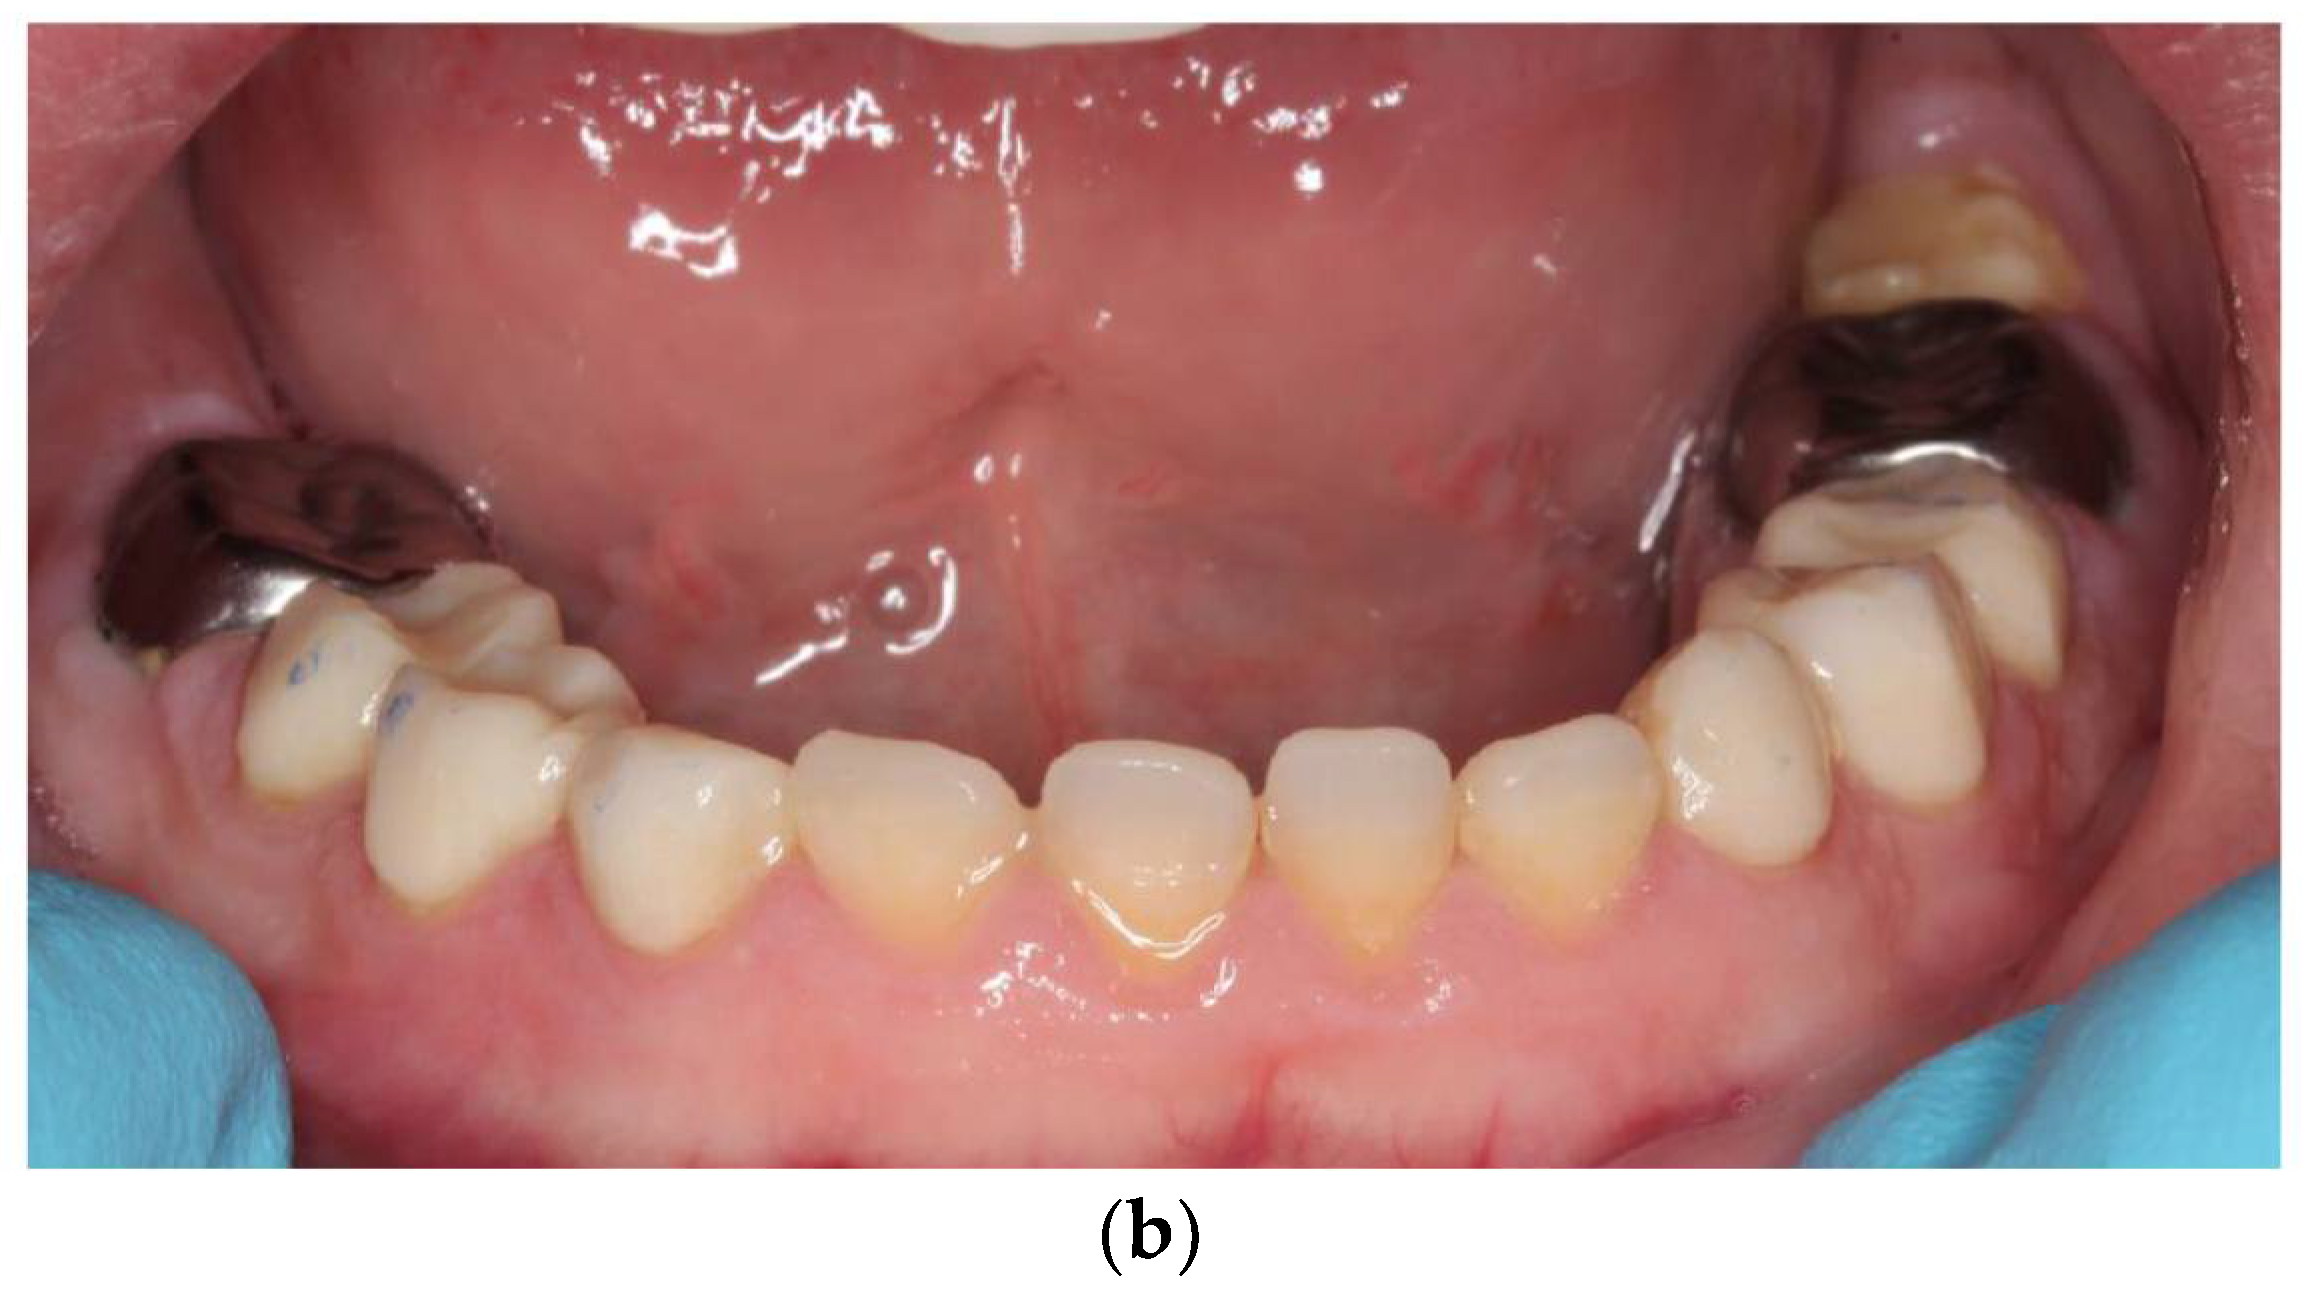

2.1. Case Report 1: Mixed Dentition

2.2. Case Report: Permanent Dentition